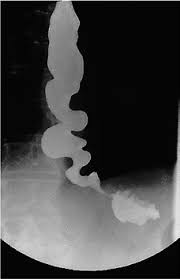

Ο “οισοφάγος Καρυοθραύστης” μπορεί να προκαλέσει πόνο στο στήθος, δυσκολία στην κατάποση και την αίσθηση ότι το φαγητό κολλάει .Είναι συχνά εσφαλμένη διάγνωση ως καρδιακή προσβολή ή παλινδρόμηση οξέος.

Ο οισοφάγος καρυοθραύστης στοχεύει τους λείους μύες που συνήθως μετακινούν τα τρόφιμα από το λαιμό σας μέχρι το στομάχι σας. Το ίδιο ισχύει και για τον οισοφαγικό σπασμό.

«Σκεφτείτε τις διαταραχές αυτές ως ξαδέλφια».”Κανονικά, όταν καταπιείτε υγρά ή στερεά, υπάρχει μια ωραία, συντονισμένη περισταλτική κίνηση από την κορυφή, το μέσον, έως το κάτω τμήμα του οισοφάγου.”

Αλλά στον οισοφάγο, οι μυϊκές συσπάσεις είναι πολύ ισχυρές. Και στον σπασμό του οισοφάγου, οι συσπάσεις των μυών είναι πολύ γρήγορες.

Εάν ο πόνος και η δυσκολία στην κατάποση επιμένουν, συχνά σταματούν εκεί και υποθέτουν ότι είναι ο οισοφαγικός σπασμός. “Αλλά η μανομετρία είναι ο μόνος τρόπος για να διαγνώσετε αυτές τις μυϊκές διαταραχές”